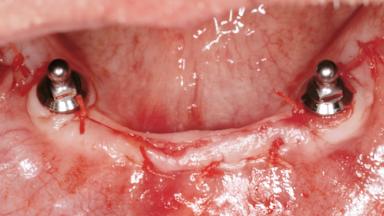

Early Loading of Two Implants in the Mandible and Final Restoration with a Retentive-Anchor-Supported RDP

A 63-year-old male edentulous and maladaptive patient presented with an inability to wear his existing complete maxillary and mandibular dentures. He had been edentulous for 41 years, and there had been three unsuccessful attempts by dentists to provide complete dentures for him. Efforts to wear both complete dentures were always initially encouraging, but over time, he invariably found that he was unable to wear the complete mandibular denture, and this pattern had persisted for 20 years. After seeing local newspaper advertisements, he requested having his complete mandibular denture stabilized with implants.

# of Implants 2

Type of Implants One-Piece

Attachment One-Piece

Modality 2 interforaminal implants